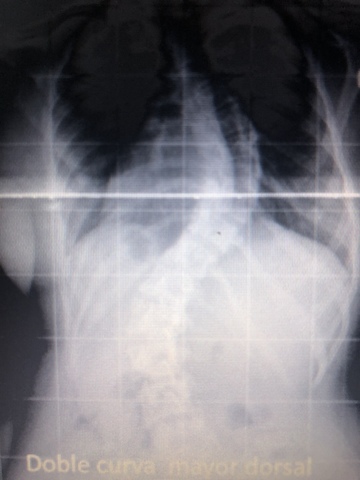

• Escoliosis

Escoliosis

Me detectaron escoliosis y estuve dos años con un corsét, finalmente me operé